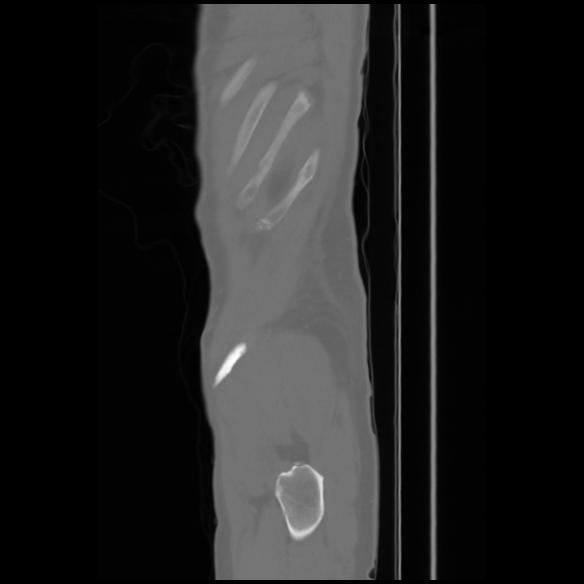

7 CUERPO,CE,Sagittal,3.000,CUERPO,Sagittal,